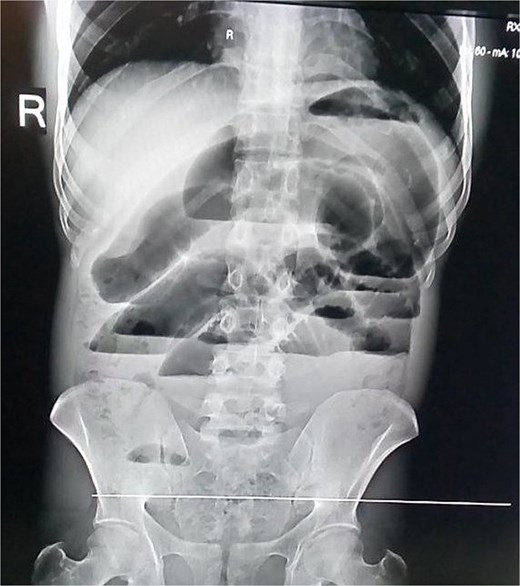

Laboratory investigations, including complete blood count and serum chemistry, were within normal limits. An abdominal X-ray showed markedly dilated loops of small bowel with multiple air-fluid levels (Fig. 1), confirming SBO. A CT scan of the abdomen and pelvis was planned for further evaluation, but could not be obtained due to unavailability. The patient was resuscitated with intravenous fluids, nasogastric decompression, and broad-spectrum antibiotics and was taken emergently for surgery.